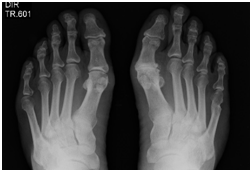

At the first day of treatment the patient was oriented to 30minutes sand walk at the beach once per week. According to Borg scale for pain in the second day the patient has grade 8 to the left inferior member (LIM) and 4 to the right inferior member. The Borg number falls to 5 in the third session to LIM. In the fifth session no pain was related by patient. It was use elastic therapeutic bandage (teraband) to sustain the foot under the metatarsus in both members. In the seventh day the patient managed to wear closed shoes without bother. In the re-evaluation with x-ray shows reduction of the bone protuberance on the Hallux (Figure 1 & 2).

Figure 1 X-ray of the feet showing the abnormal growing of a protuberance at the hallux in both feet. Note the deformity.